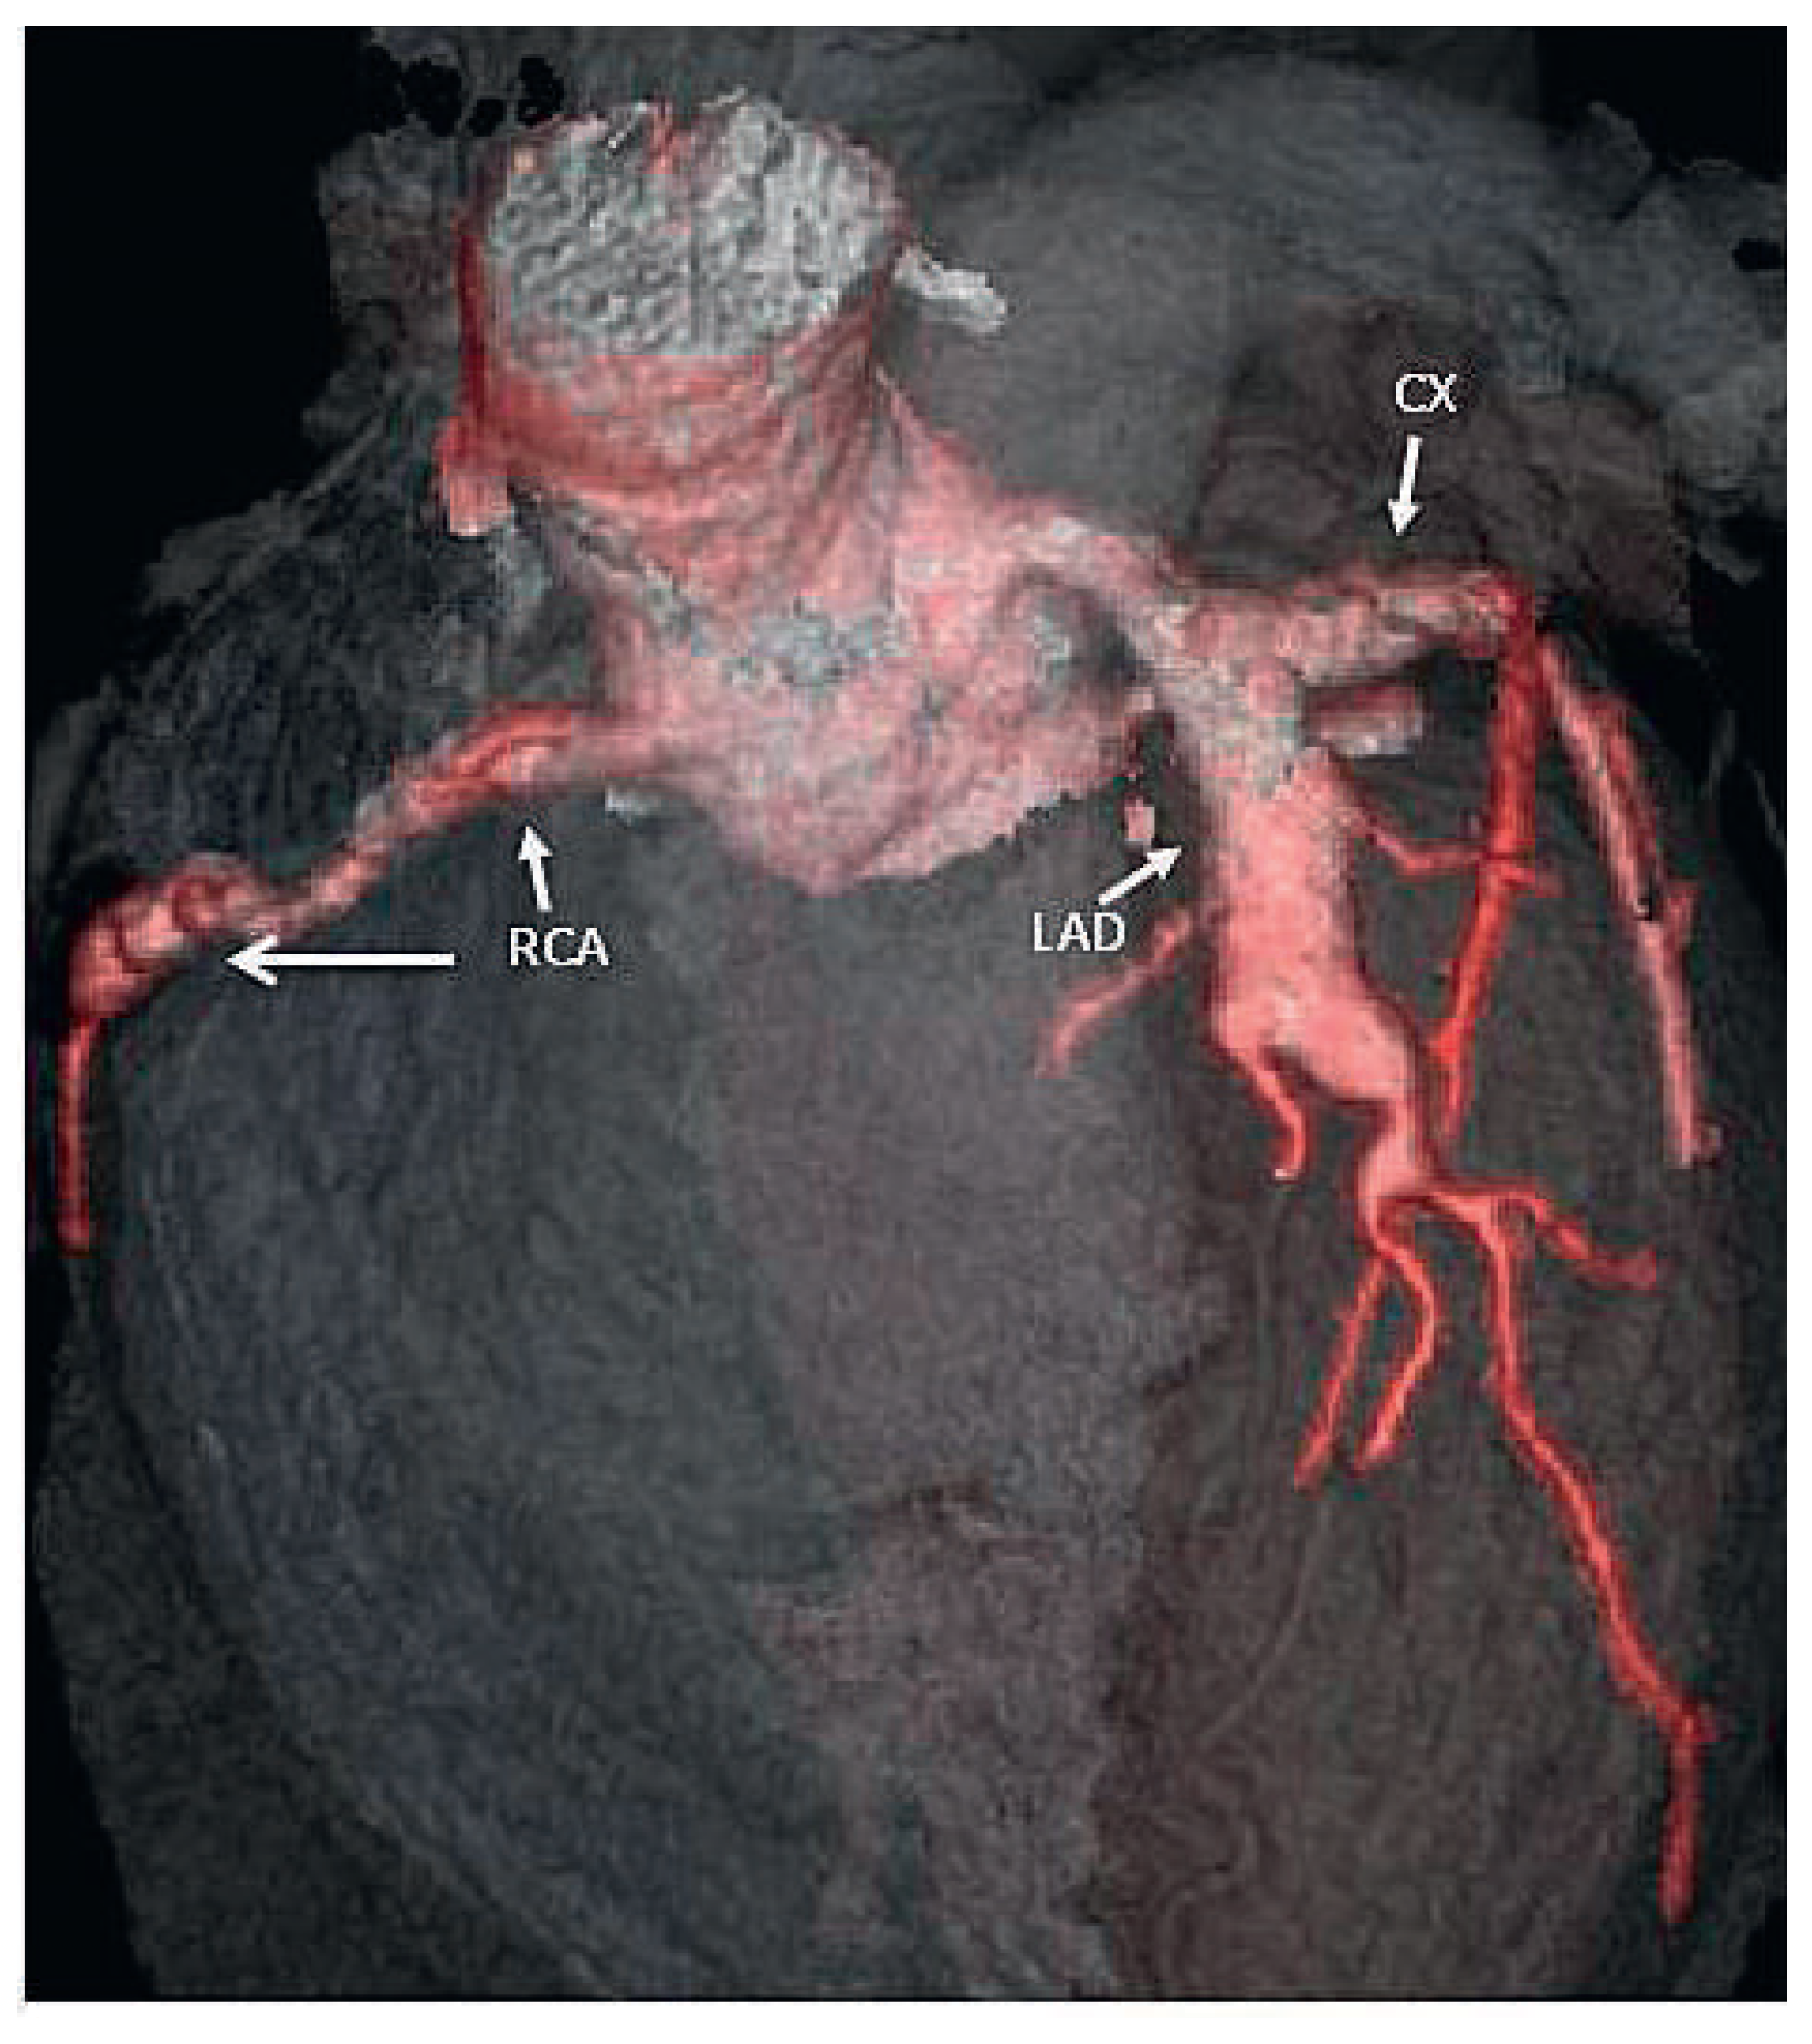

On the tenth day, we performed transthoracic echocardiography (Figure 1 and Figure 2), which revealed normal biventricular size and function, without hypokinesia. There was no pericardial effusion, no valvular disease, but a proximal enlargement of the left anterior descending coronary artery (LAD) was visualised. On the same day, because all these elements suggested Kawasaki disease (KD), treatment with intravenous polyvalent immunoglobulin (IVIG 2 g/kg as a single infusion: Privigen 70 g) and high-dose aspirin (80 to 100 mg/kg/d: 750 mg four times a day for eight days) was started, with rapid resolution of symptoms and apyrexia within 24 hours. Cardiac computed tomography (CT; Figure 3) showed three-vessel aneurysmal coronary artery disease (CAD) including a giant aneurysm of the proximal LAD (9 mm), an aneurysm of the circumflex artery (6 mm) and two aneurysms of the right coronary artery (4 and 5 mm). There was no vascular involvement in the cerebral and abdominal magnetic resonance imaging (MRI).

Figure 3.

3D-computed tomographic reconstruction showing aneurysms of the left anterior descending (LAD), the left circumflex (CX) and the right coronary artery (RCA).